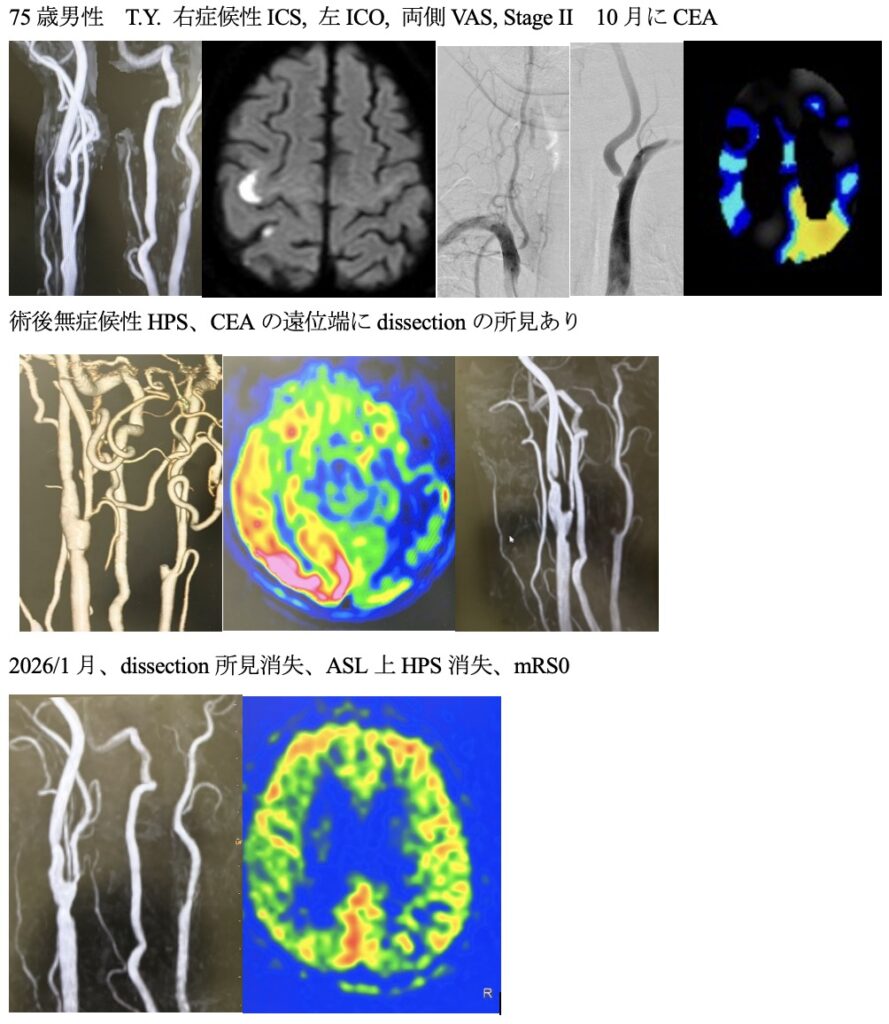

251021火 75歳男性、左内頸動脈閉塞、両側椎骨動脈狭窄を伴う右内頸動脈狭窄症に対してCEAを行いました。 2026 1/23 内頸動脈狭窄 2025年12月11日2026年1月23日多発狭窄で血行力学的脳虚血も合併している脳梗塞発症の右内頸動脈狭窄症に対して血栓内膜剥離術を行いました。術後、無症状ですがSPECT上過還流の所見が出ましたので、1週間以上降圧管理を行い、無事何事もなく退院されました。ScreenshotScreenshotScreenshotScreenshotScreenshotScreenshotScreenshotScreenshot 内頸動脈狭窄 よかったらシェアしてね! URLをコピーしました! URLをコピーしました! 251019日 今週は越前陶芸の里と漁り火温泉に行きました。 251024金 橋本信夫先生に久しぶりにお会いしました。 この記事を書いた人 kikuta 関連記事 血栓内膜剥離術(CEA)を行いました。 2025年2月26日 右内頸動脈狭窄をCEAしました 2025年2月4日 240416火 続いて、84歳の症候性内頸動脈狭窄をCEAを行いました。 2025年1月29日 久しぶりにCEAをやりました 2023年9月27日